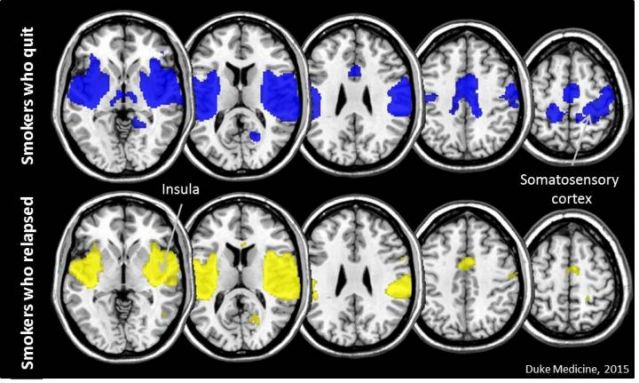

اما ۴۴ نفر از آنها موفق شدند که سیگار کشیدن را بطور موفقیت آمیزی کنار بگذارند؛ نتایج مطالعه محققان از روی ام.آر.آی این افراد نشان داد که در تمامی آنها دو قسمت از مغزشان به نام اینسولا و قشر somatosensory ارتباط زیادی بهم داشت.

این مطالعه نشان داد که ارتباط میان این دو قسمت از مغز برای ترک سیگار مهم است.

از سوی دیگر قشر حسی-پیکری (somatosensory) مغز ، کنترل کارکردهای حسی و حرکتی را بر عهده دارد. این مطالعه نشان داد که ارتباط میان دو بخش اینسولا و قشر somatosensory در افرادی که موفق شدند سیگار را ترک کنند، بیشتر بود.